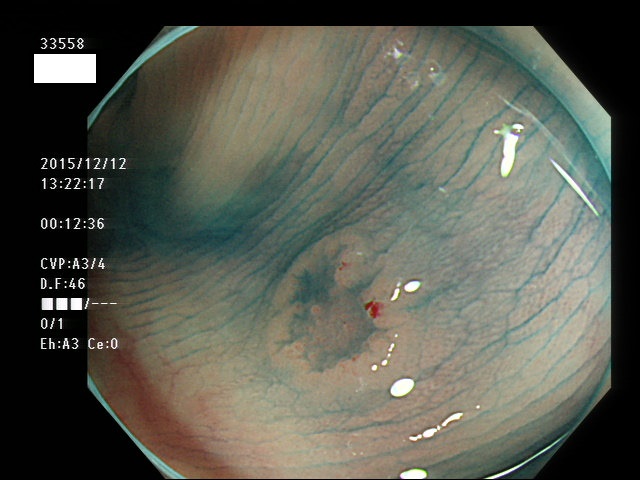

上記100名より抽出した平坦・陥凹型腺腫(=癌化の危険が高いが見落としやすい病変)の内視鏡写真

33500 33501 33505 33507 33508 33509 33510(SSA/Pのみ) 33511 33512 33514 33517 33519 33523 33528 33529 33530 33535 33537 33538 33539 33540 33544 33546 33547 33548 33549 33550 33552 33553 33555 33558 33559 33562 33563 33567 33571 33576 33578 33580 33581 33583 33585 33586 33587 33589 33590 33594 33595 33596 33599 ・・・・・・の50名